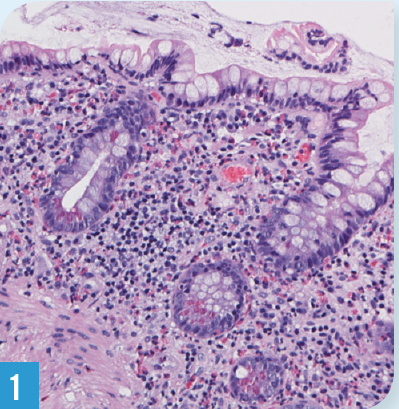

A CT scan and MRI of the abdomen-pelvis showed postsurgical changes with no acute abnormalities. A duplex ultrasound revealed normal pre/postprandial celiac and superior mesenteric blood flow. An upper endoscopy and ileoscopy were reported as grossly normal. Random biopsies of stomach and duodenum were normal, but of the ileum revealed marked eosinophilia (Figure) in the lamina propria, without evidence of cryptitis, abscess, or granuloma.